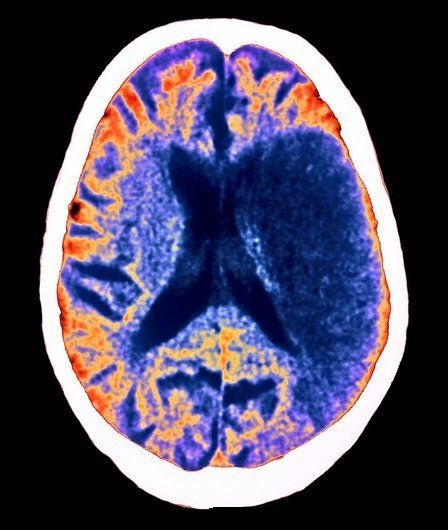

Перфузионная компьютерная томография является разновидностью КТ-ангиографии, дающая возможность исследования гемодинамики головного мозга на капиллярном уровне. Методика основывается на количественной оценке изменений рентгеновской плотности ткани мозга, по сосудам которой проходит внутривенно введенное контрастное вещество. В результате различного количества накопленного контраста становится возможным применение различных математических моделей с последующим построением трехмерных перфузионных карт, что позволяет широко применять этот метод изучении измененного кровотока, и в частности в диагностике ишемического инсульта.

При этом основные параметры перфузии связаны следующим соотношением: CBV=CBFхMTT. По каждому из этих основных параметров строится соответствующая перфузионная карта, по которой впоследствии можно наглядно оценивать динамику процесса. Помимо данных показателей, учитывается также степень стеноза устья внутренней сонной артерии. При наличии риска развития инсульта будет наблюдаться снижение CBF, нормальные или чуть повышенные показатели CVD, а, следовательно, и возрастающий MTT. Если же инсульт уже развился и произошел некроз мозговой ткани, то будут наблюдаться пониженный CBF и CBV, а MTT будет нормальным или чуть повышенным. Обратимым является ишемическое повреждение при показателях – 10-25 мл/100 г ткани/мин, необратимым– < 10 мл/100 г ткани/мин.